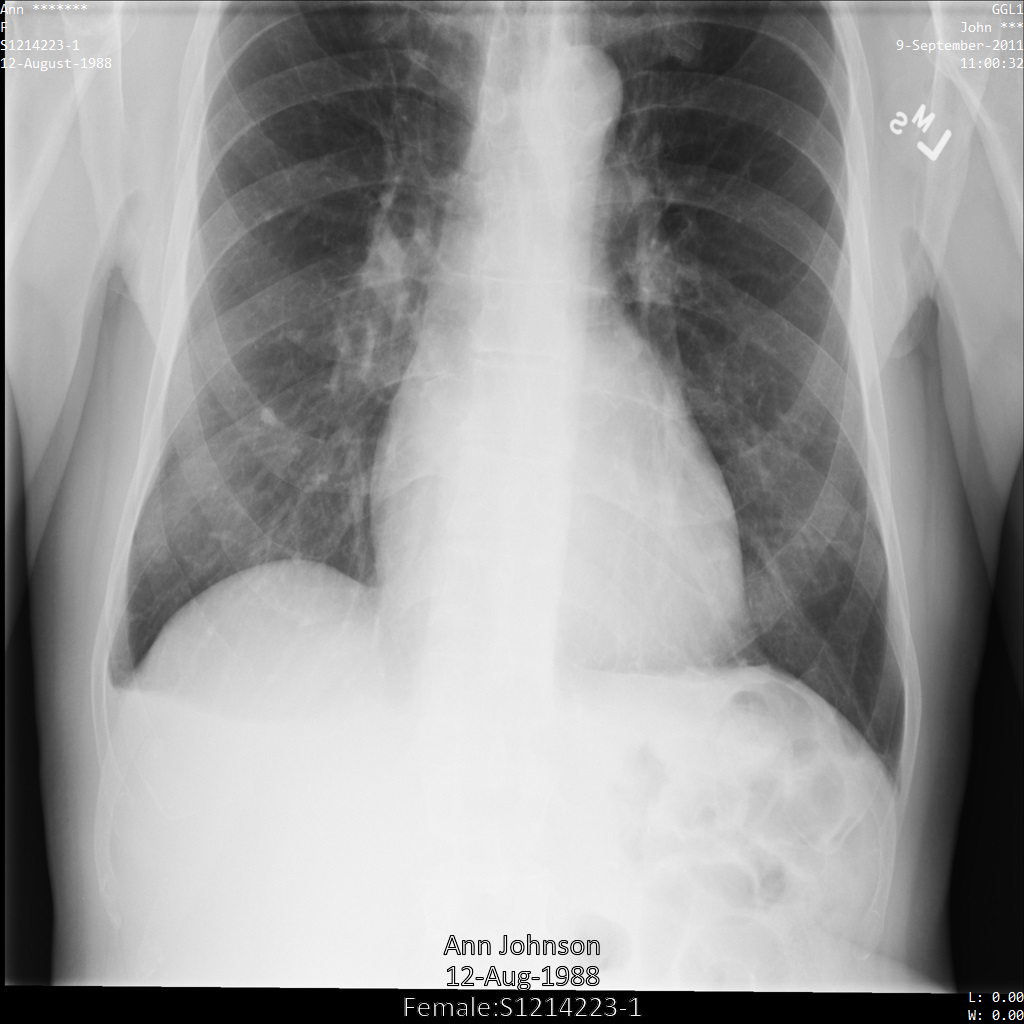

In jedem der folgenden Abschnitte finden Sie Beispiele zur De-Identifikation von DICOM-Daten mithilfe verschiedener Methoden. Für jedes Beispiel wird eine Ausgabe des de-identifizierten Images bereitgestellt. In jedem Beispiel wird das folgende Originalbild als Eingabe verwendet:

Sie können das Ausgabebild jedes De-Identifizierungsvorgangs mit diesem Originalbild vergleichen, um die Auswirkungen des Vorgangs zu sehen.

Nachdem Sie das Image an die Cloud Healthcare API gesendet haben, wird es wie folgt angezeigt. Während die Metadaten, die in den oberen Ecken des Bildes angezeigt werden, entfernt wurden, bleiben die eingebrannten geschützten Gesundheitsinformationen (PHI) unten im Bild erhalten. Informationen zum Entfernen des eingebrannten Texts finden Sie unter Eingebrannten Text aus Bildern entfernen.